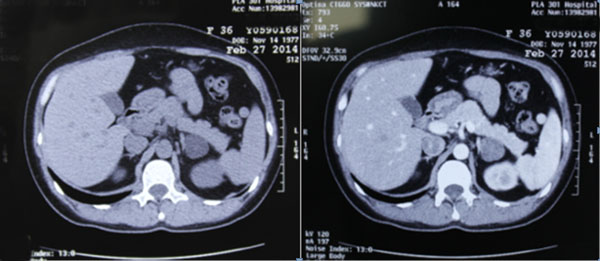

【资料】301医院教学案例:原发性醛固酮增多症

图片尺寸600x261